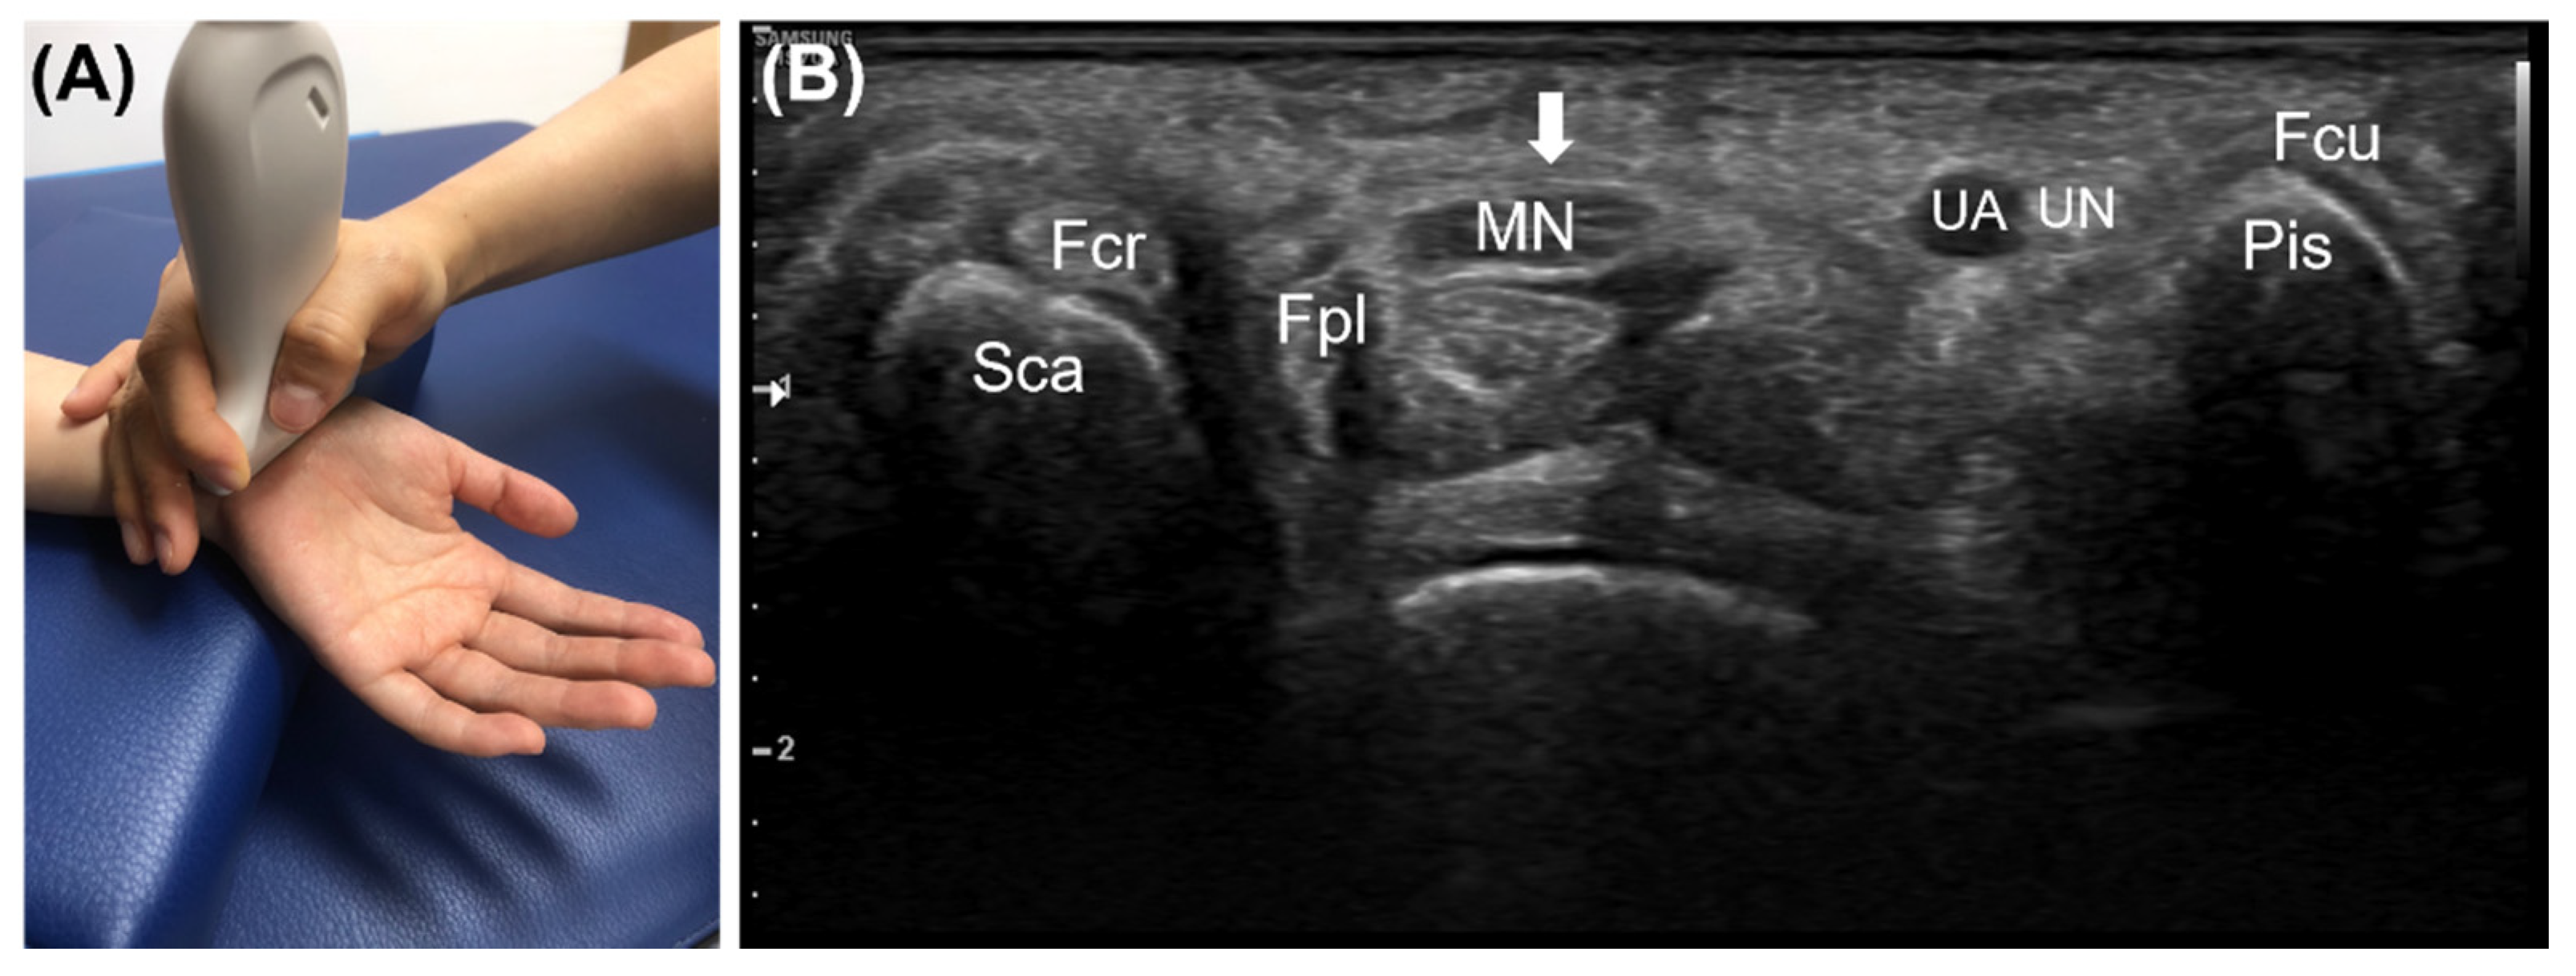

| 10. Correct view of the (1) scaphoid, (2) pisiform, (3) median nerve, (4) ulnar artery, (5) flexor retinaculum, (6) flexor pollicis longus, (7) ulnar nerve, (8) flexor digitorum superficialis, flexor digitorum profundus, (9) flexor carpi radialis, (10) flexor carpi ulnaris | 3 | 2.33 ± 0.74 | |

| 11–1. Connecting the top of the scaphoid and the pisiform with a line | 1 | 0.76 ± 0.43 | |

| 11–2. Measuring the vertical distance between the line connecting the top of the scaphoid and the pisiform and the flexor retinaculum | 1 | 0.64 ± 0.48 | |